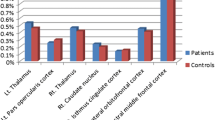

Corresponding ICA images were independently selected from the two groups according to the templates presented by GIFT. Forty-eight components were obtained, 21 of which were selected as the resting-state network: 2 components in the language network, 3 in the default mode network (DMN), 3 in the visual network, 3 in the executive network, 3 in the sensorimotor network, 2 in the salience network, 4 in the attention network, and the remaining component in the cerebellum (Fig. S1). Age, gender, and BMI were used as covariates for group comparison between patients and controls and the differences are shown in Table 2 and Fig. 1. Compared with controls, decreased FC in the right caudate within the salience network (Fig. 1A) and decreased FC in the left medial frontal gyrus within executive network (Fig. 1B) were found in narcolepsy patients, while increased FC in the bilateral middle frontal gyrus within the executive network (Fig. 1B) was also found in patients.

Sparsity values were selected in the analysis of nodal topological properties. Many brain nodes showed altered topological properties between narcolepsy patients and healthy controls. Specifically, eight overlapping nodes – the bilateral inferior frontal gyrus (IFG), right anterior cingulate gyrus (ACG), left supplementary motor area (SMA), right calcarine fissure (CAL), and bilateral basal ganglia – had the same alterations in centrality measurements (BC and DC) in patients and controls (Fig. 3 and Table 3). Meanwhile, six overlapping nodes – the left IFG, left ACG, left posterior cingulate gyrus (PCG), bilateral posterior central gyrus (PoCG), and left caudate (CAU) – had the same alterations in clustering measurements (NCC and NE) in patients and controls (Fig. 4 and Table 3).

Eight overlapping regions in centrality measurements (BC and DC) and their functional connectivity in comparisons between healthy controls and narcolepsy patients. Scatter plots and partial correlation analysis between nodal topological or functional connectivity and severity of sleepiness in narcolepsy. FC, functional connectivity; ESS, Epworth Sleepiness Score; IFG, Inferior frontal gyrus; ACG, anterior cingulate gyrus; CAU, caudate nucleus; PUT, putamen; PAL, pallidum; SMA, supplementary motor area; CAL, calcarine fissure; L, left; R, right.

Six overlapping regions in clustering measurements (NCC and NE) and their functional connectivity in comparisons between healthy controls and narcolepsy patients. Scatter plots and partial correlation analysis between nodal topological or functional connectivity and severity of sleepiness in narcolepsy. FC, functional connectivity; ESS, Epworth Sleepiness Score; IFG, inferior frontal gyrus; ACG, anterior cingulate gyrus; CAU, caudate nucleus; PCG, posterior cingulate gyrus; PoCG, postcentral gyrus; L, left; R, right.

Nodal Functional Connectivity Analysis

Among the eight overlapping nodes in centrality differences between groups, increased FC among anterior brain areas (IFG, ACG, SMA, and basal ganglia) was found in narcolepsy patients compared with healthy controls, while decreased FC between the right CAL and some anterior brain areas (left IFG, SMA, and ACG) was detected in patients compared with controls (Fig. 3 and Table S1). Among the six overlapping nodes in clustering differences between groups, decreased FC between the left ACG and left PCG as well as FC among the bilateral PoCG was found in patients compared with controls, while FC between the left IFG or left ACG and the bilateral PoCG was higher in patients than in controls. Moreover, FC between the left PCG and bilateral PoCG as well as FC between the left IFG and left CAU was also higher in patients than in controls (Fig. 4 and Table S1).

Partial Correlation Analysis

In the graph theoretical analysis results from narcolepsy patients, partial correlation showed that the mean REM sleep latency from MSLT was negatively correlated with DC in the left putamen (r = –0.471, P = 0.015, Fig. 3), the mean REM latency from MSLT was positively correlated with NE in the left PCG (r = 0.722, P < 0.001, Fig. 4), and the ESS was positively correlated with NCC in the left ACG (r = 0.489, P = 0.011, Fig. 4), and was negatively correlated with NE in the left PoCG (r = –0.438, P = 0.025, Fig. 4) and NE in the right PoCG (r = –0.51, P = 0.008, Fig. 4). In the FC analysis results from narcolepsy patients, the mean sleep latency was negatively correlated with FC between the left IFG and left CAU (r = –0.478, P = 0.013, Fig. 3). The mean REM sleep latency was positively correlated with FC between the left SMA and right CAL (r = 0.398, P = 0.044, Fig. 3) and the mean REM sleep latency was negatively correlated with FC between the left ACG and left PoCG (r = −0.494, P = 0.01, Fig. 4) as well as between the left ACG and right PoCG (r = –0.422, P = 0.032, Fig. 4). ESS was positively correlated with FC between the left SMA and right ACG (r = 0.439, P = 0.025, Fig. 3). Correlation analysis between nodal topological connectivity or FC and ESS among narcolepsy patients is also shown in Table S2.

We found decreased FC in the left medial frontal gyrus within the executive network and decreased FC in the right caudate within the salience network in adult narcolepsy patients compared with healthy controls. Compared with controls, increased FC in the bilateral middle frontal gyrus within the executive network was detected in the narcolepsy patients.

Alterations of centrality demonstrated overlapping areas in the bilateral IFG, right ACG, left SMA, bilateral basal ganglia, and right CAL between patients and controls. Excitatory hypocretin innervation of visual neurons has been described in a previous study [55], so we infer that the decreased BC and DC in the right CAL may be related to the reduced excitation by hypocretin in narcolepsy. Increased BC and DC in the right ACG is consistent with a positron emission tomography study, in which hyper-metabolism in the anterior cingulate cortex was revealed in narcolepsy patients under fully awake conditions [6]. The increased BC and DC in the bilateral IFG is partially in agreement with the ICA results from the present study, in which increased FC in the bilateral middle frontal gyrus also reflected the subjective effort to maintain alertness, and methodological differences in ICA and graph theoretical analysis led to the diversity of results in ICA and centrality measurements in the bilateral frontal lobe. Partial correlation analysis showed that DC in the left putamen was negatively correlated with mean REM sleep latency among narcolepsy patients, and this indicated that increased DC in the left putamen might be associated with the pathophysiology of sleepiness in narcolepsy.

Hypo-excitability in the sensorimotor cortex due to deficient hypocretin excitatory innervation has been reported in narcolepsy by transcranial magnetic stimulation [56], which could explain the reduced NCC and NE in the bilateral PoCG in the present study. Partial correlation analysis also suggested that NE in the bilateral PoCG was negatively correlated with ESS among patients, indicating that decreased NE in the postcentral gyrus on both sides was associated with the severity of subjective sleepiness in narcolepsy. PCG is a core node in the DMN, and a disrupted DMN has been shown to be disease-specific for narcolepsy in an EEG-fMRI study [57]. Moreover, partial correlation analysis showed that NE in the PCG is positively correlated with the mean REM sleep latency, indicating that reduced NE in the PCG was also associated with the pathophysiology of sleepiness in narcolepsy. Enhanced NE and NCC in the left ACG, left IFG, and left basal ganglia was consistent with the increased BC and DC within these areas in the present study; also, the increased NE in left ACG was correlated with the severity of subjective ESS.

Nodal Functional Connectivity in Comparison of Narcolepsy Patients with Healthy Controls

An increased FC between the right ACG and bilateral basal ganglia (left putamen and right pallidum) was found in narcolepsy patients compared with healthy controls. Both the ACG and basal ganglia are core components of the salience network [50, 51], and increased FC among these areas is consistent with the results of previous narcolepsy studies of the salience network [48, 53]. Increased FC between the bilateral IFG and right ACG as well as the basal ganglia implies an enhanced connection between the executive and salience networks, and this might partially explain the increased FC in the bilateral frontal lobe within the executive network in our ICA results. Both increased FC within the salience network and between the executive and salience networks indicate the subjective effort to maintain wakefulness during the MRI scan [49, 52]. Especially, FC between the left IFG and left CAU was negatively correlated with REM sleep latency in narcolepsy patients, demonstrating that increased FC between the left IFG and left CAU might be associated with the pathophysiology of sleepiness in narcolepsy. The SMA is involved in motion adjustment and coordination [58]. FC between the left SMA and right ACG was positively correlated with REM sleep latency, and the FC between the left SMA and right CAL was positively correlated with ESS in narcolepsy patients, indicating that abnormal activity in the SMA and its connections might also be associated with the abnormal sleepiness in narcolepsy. Also, decreased FC between the right CAL and left IFG as well as decreased FC between the right CAL and right ACG was found in patients compared with controls. This decreased FC might be correlated with the decreased centrality in the right CAL just as in the graph theoretical analysis results in the present study.

Decreased FC among the bilateral PoCG was in accord with the changes in topological properties in the bilateral PoCG, which is associated with hypo-excitability within these areas due to hypocretin dysfunction [56]. Decreased FC between the left PCG and left ACG demonstrated a potential dysfunctional connection between the salience network and the DMN; this has rarely been reported in previous studies. FC between the left ACG and bilateral PoCG was negatively correlated with REM sleep latency, which implied that increased FC between the left ACG and bilateral PoCG might also be associated with the pathophysiology of sleepiness in narcolepsy. Increased FC between the left PCG and bilateral PoCG might be a compensation for decreased NE/NCC within these areas in narcolepsy patients.

Increased ESS, and shortened sleep latency and REM sleep latency are all parameters that indicate the severity of narcolepsy. Also, a shortened REM sleep latency is a clinical characteristic of narcolepsy. In our results, for nodal topological properties, the NCC value in the left ACG and the NE value in the bilateral PoCG were each correlated with ESS, suggesting that subjective sleepiness measurement is strongly associated with network alterations in these brain areas. The DC value in the left PUT and the NE in the left PCG were each correlated with REM sleep latency, suggesting that network changes in both areas may be a specific indicator for evaluating the severity of narcolepsy. As for FC, an increase between the left SMA and right ACG was positively correlated with ESS, implying subjective sleepiness measurement is also associated with altered nodal connectivity. Increased FC between the left IFG and left CAU was negatively correlated with sleep latency, indicating that the FC changes between the frontal cortex and basal ganglia may be one of the parameters describing the severity of narcolepsy. Meanwhile, the decreased FC between the left SMA and right CAL was positively correlated with REM sleep latency, and the increased FC between the left ACG and bilateral PoCG was negatively correlated with REM sleep latency, indicating that altered FC may also be a specific indicator for evaluating the severity of narcolepsy.